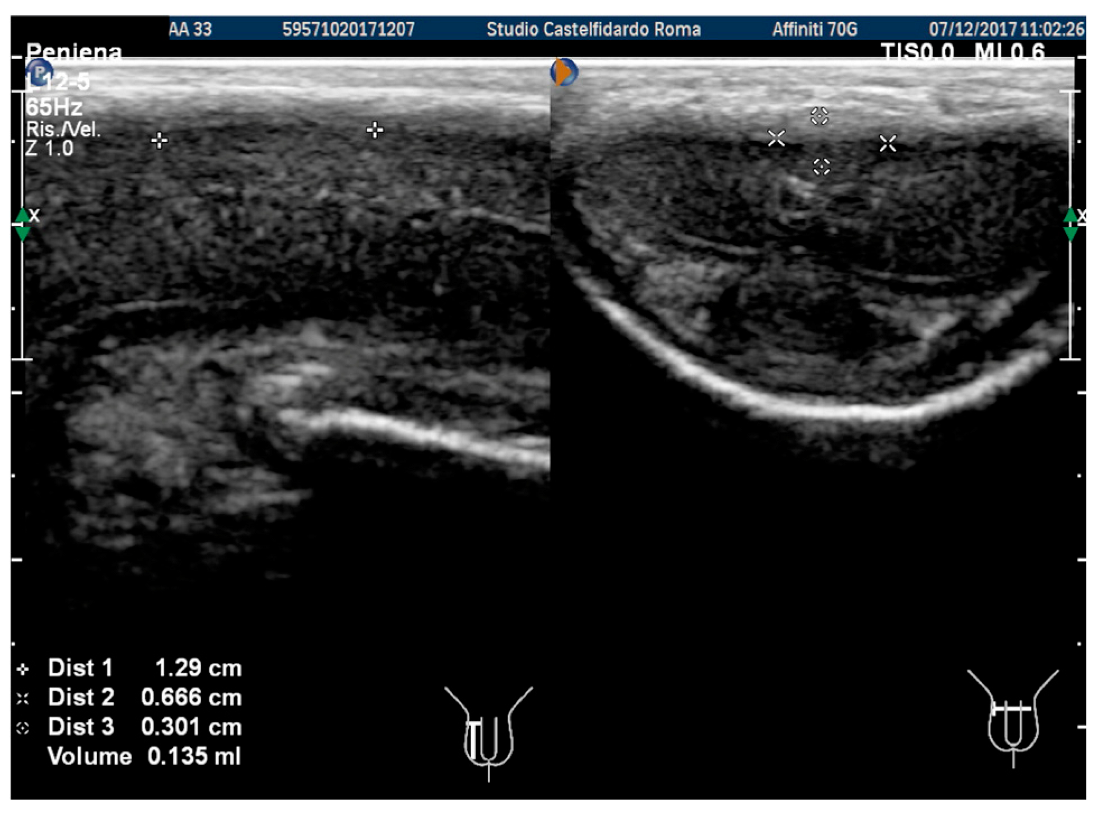

| 2 | 32 years | lichen sclerosus, chronic prostatitis | Proximal third | (A) 16.4 × 8.27 × 3.09 mm volume = 219 mm3 | (A) 10-degree left curvature | (A) score 3 | (A) score 26 | 2 years and 9 months | orally: Silymarin 400 mg + Ginkgo biloba 250 mg + Propolis 600 mg + Bilberry 160 mg + Vitamin E 800 IU/once a day, for 33 months. + topically: Propolis creme/twice a day/for 33 months. + peri-plaque penile injections: Pentoxifylline 100 mg (30 G needle) every 15 days for 6 months, and then monthly for 12 months, and then 1 injection every other month. for 12 months (total = 30 injections) |

| (B) No plaque detected | (B) None | (B) score 0 (after six months) | (B) score 28 | ||||||